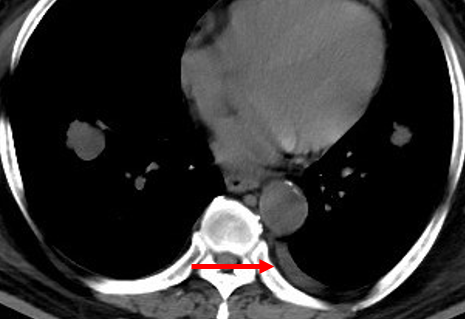

2017.07.10:

2019.02.14: